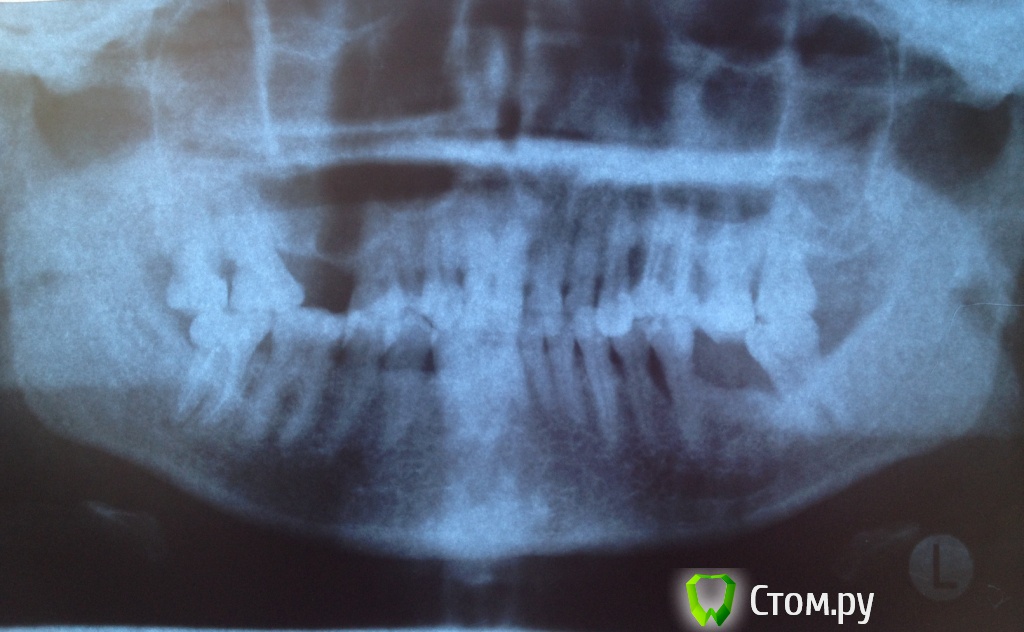

Нади999 Опубликовано 26 апреля, 2014 Поделиться Опубликовано 26 апреля, 2014 Добрый день. Меня зовут Надежда, 32 года.Прошу помочь советом, возможна ли имплантация в моем случае (снимок прилагаю).У меня флюороз, в связи с чем зубы подвержены разрушению (поражение эмали). Со временем произошло снижение прикуса в связи с частым терапевтическим лечением.2 года назад поставили диагноз пародонтоз, предположительно в следствии неправильного прикуса и доп. нагрузки на оставшиеся зубы. Регулярно провожу чистку ультразвуком, слежу за гигиеной полости рта в домашних условиях (отвары, зубные ершики и т.д.) - помогает на какое-то время. Комплексно к решению этой проблемы до настоящего момента не подходила.В данный момент планирую оперативно заняться вопросом восстановления зубного ряда.Подскажите, с чего стоит начинать в моем случае!?Заранее благодарю за любую помощь. Ссылка на комментарий

red_butler Опубликовано 26 апреля, 2014 Поделиться Опубликовано 26 апреля, 2014 начать с нового снимка, лучше на цифровом носителе Ссылка на комментарий

faity Опубликовано 8 мая, 2014 Поделиться Опубликовано 8 мая, 2014 согласен с доктором.плюс нужен визуальный контроль. фото ещё сделайте или на консультацию к кому-нибудь запишитесьисключительно по снимку сложно судить состояние пародонта Ссылка на комментарий